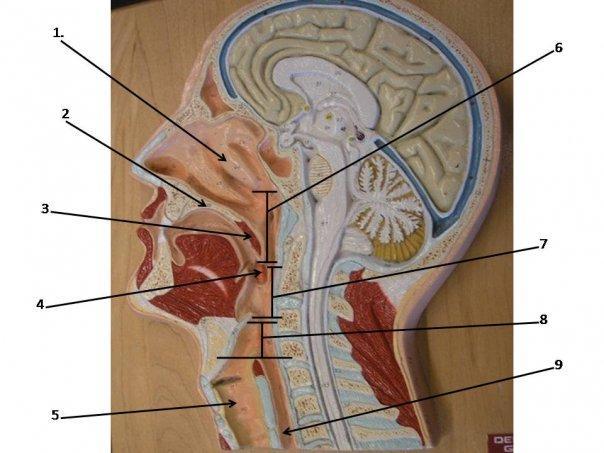

Epiglottis

Esophagus

Hard/soft palate

Inferior/middle/superior concha (s.) conchae (pl.)

Larynx

Nares

Nasal Cavity

Nasal septum

Naso/oro/laryngo-phraynx

Oral Cavity

Paranasal sinuses

Tongue

Trachae

Uvula

Vestibule (of nasal cavity)

Vocal folds (=vocal cords)